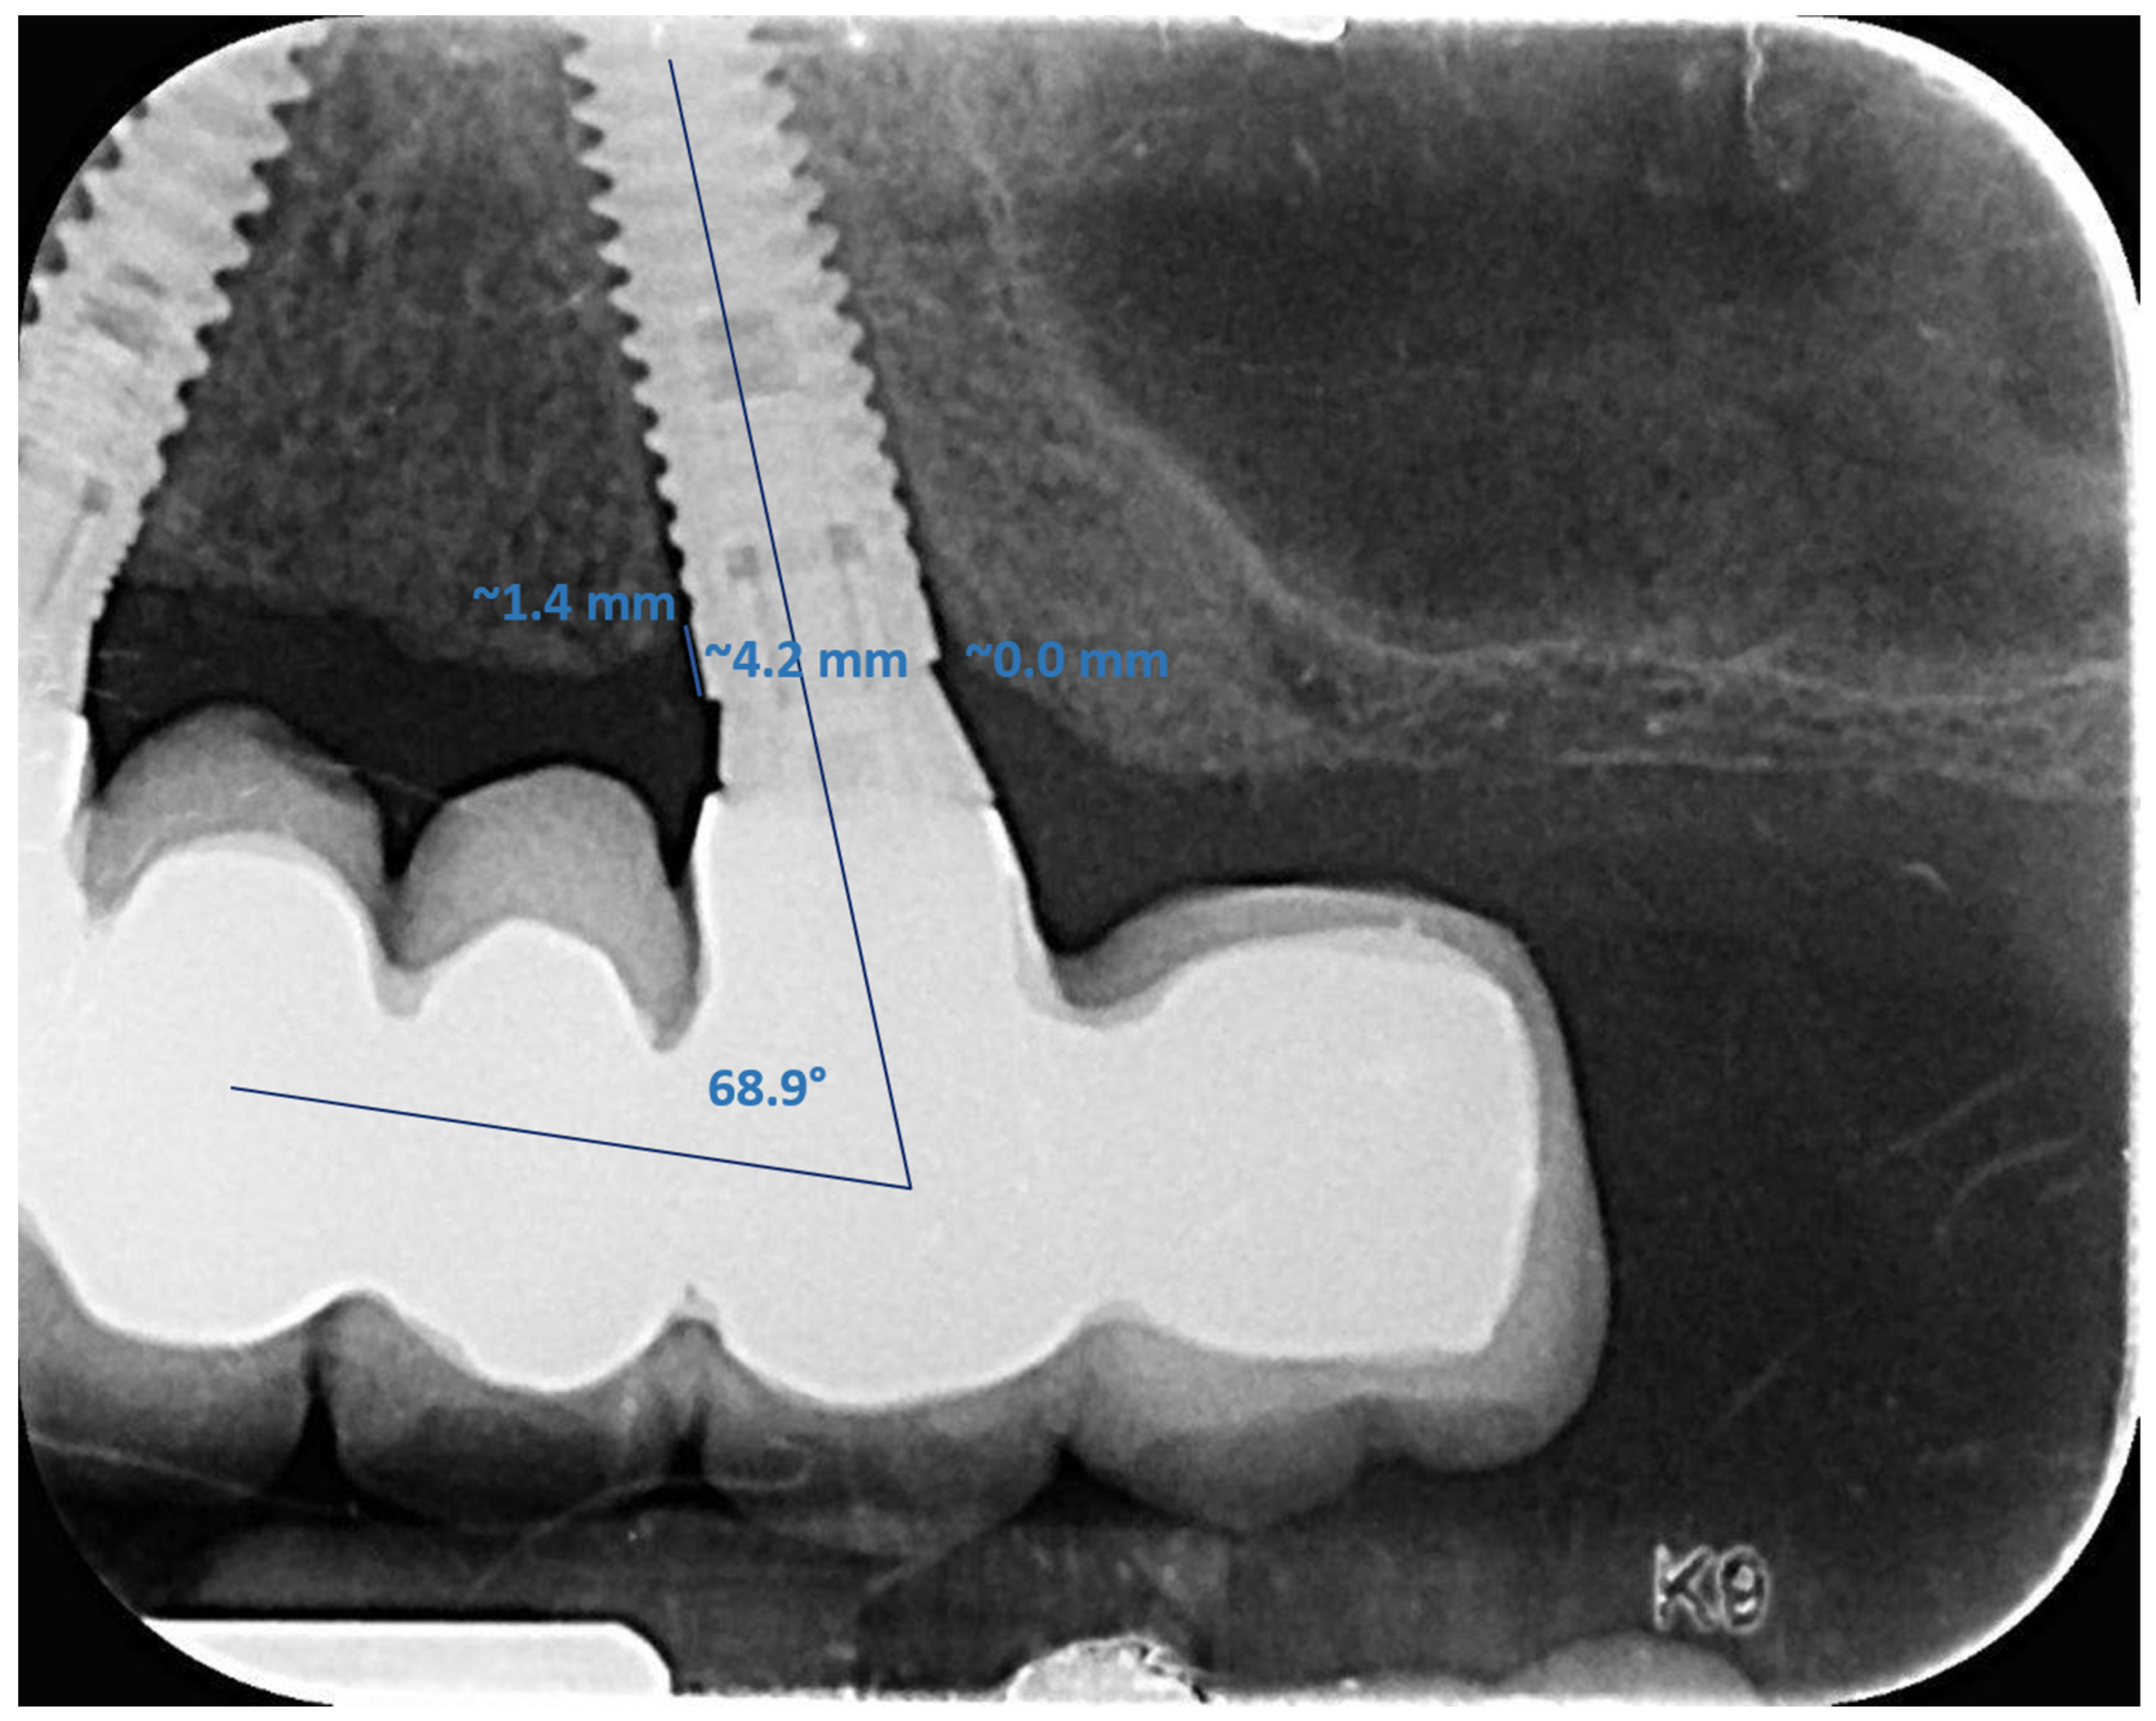

2.4.4. Radiographic Measurements

3.4. Marginal Bone Loss

| Implant angle | <15° (85) | 0.08 | 0.13 | 0.12 | 0.20 |

| ≥15° (44) | 0.07 | 0.14 | 0.07 | 0.12 | |

| p | 0.63 | 0.08 | |||